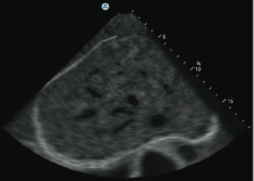

ABDOMINAL MODULE :

The Abdominal Module, featuring 8 cases, will offer a comprehensive training environment incorporating diverse anatomies and pathologies.

The simulation environment combines high level of realism with advanced educational aids, featuring:

- The clinical cases feature a complete, dynamic anatomical environment.

- Case severity customisation - providing the opportunity to train on multiple scenarios using each single case.

- Training scenarios featuring both adults and paediatric Virtual Patient cases.

- The clinical cases will present scenarios such as: abdominal pain, abdominal distension, abnormal test results, abnormal liver function and more.

- With findings such as Abdominal aortic aneurism, Abdominal aortic dissection / rupture, Fatty liver, Liver mass, Renal abnormalities, Gallbladder abnormalities and more.